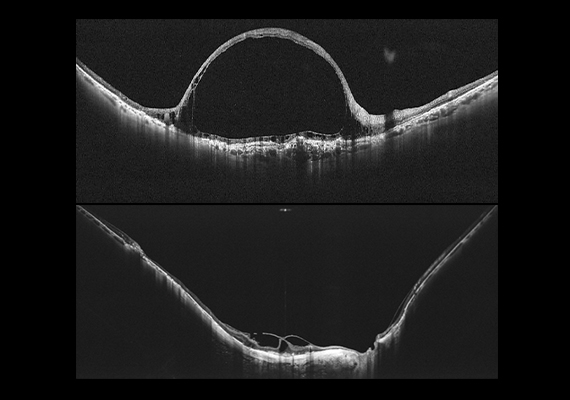

With Xephilio OCT-S1 revolutionary swept-source technology, it is possible to capture wide-field images (equalling an 80° viewing angle, up to 5.3 mm depth and 23 mm wide) with superior penetration of dense objects and provides outstanding tomographic images in a single scan. This allows wide-spread non-perfused areas (even small capillaries) to be visualised which is useful in diagnosing diabetic retinopathy and retinal vein occlusion.